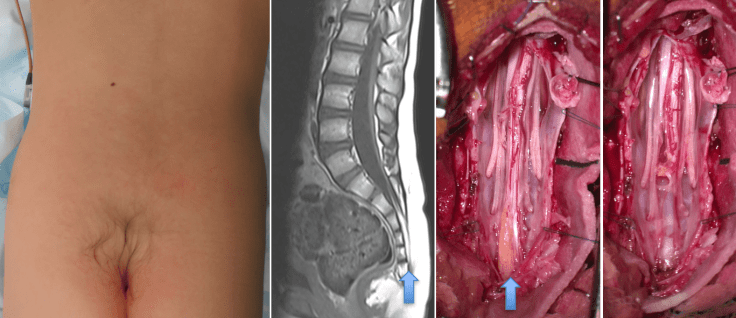

on diagnostic la rétention médullaire devant une anomalie cutanée très bas située (en regard du coccyx), une pilosité anormale, ou un tableau de moelle attachée.

il est chirurgical. on trouve un filum épais qui se continue par un tissus médullaire en dessous des dernières racines qui sortent du cul-de-sac sacré. cette moelle n’est pas fonctionnelle.